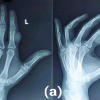

The reported case is for a 77-year-old Indian lady who presented with recurrent progressively enlarging ankle mass of 19 years duration, for which she underwent surgery 15 years ago. Even though the Swelling is not associated with pain, it is progressively increasing in size, limiting her range of motion in the left ankle. On examination, a firm, non-tender mass is present on the medial side of the left ankle joint without any signs of inflammation like redness or the local rise of temperature. The mass was non-compressible, immobile, and did not transilluminate. A scar was present over the swelling, which healed by primary intention (Fig. 1). The clinical diagnosis suggested a soft-tissue ganglion. A radiograph showed soft-tissue opacity over the anteromedial aspect of the tibiotalar joint (Fig. 2). Magnetic resonance imaging (MRI) revealed a well-defined, multilobulated, encapsulated lesion at the tibiotalar joint’s medial side, with intra- and extra-articular components and an analogous signal intensity to fat (Fig. 3).